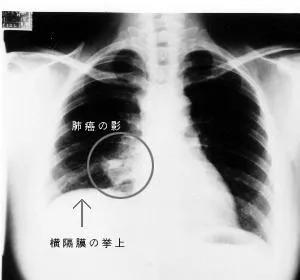

几天后,放射科医生阅片发现该患者存在肺部异常,肿瘤性病变可能,建议3个月后随诊复查,但负责临床医生并未查阅报告,没有及时告知患者发现肺部肿瘤并按时复诊。

13个月后,该患者在另一家医院检查发现肺部异常,再次前往名古屋大学医学部附属医院就诊,此时肺部肿瘤已经明显进展。尽管接受了近2年的治疗,该患者还是最终因肿瘤死亡。